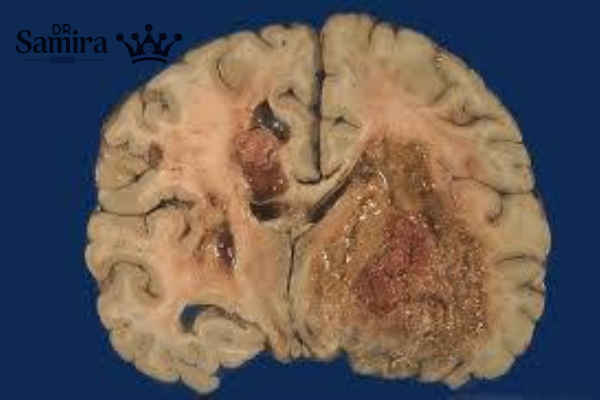

تصویربرداری MRI با تزریق گادولینیوم دقیقترین روش برای تشخیص تومورهای مغزی است. در گلیوبلاستوم، ضایعهای با مرکز نکروتیک و حاشیه نامنظم دیده میشود که پس از تزریق ماده حاجب، ناحیه حاشیهای آن بهوضوح دیده میشود. سیتی اسکن (CT) در مواقع اورژانسی، برای بررسی وجود خونریزی یا ادم مغزی مفید است.

بیوپسی (نمونهبرداری) برای تایید نهایی تشخیص انجام میشود. با بررسی بافت در زیر میکروسکوپ، سلولهای توموری با آناپلازی بالا، نکروز مرکزی و پرولیفراسیون عروقی مشاهده میشوند. آزمایشهای ژنتیکی و مولکولی برای بررسی جهش IDH، متیلاسیون MGMT و بیان EGFR به تعیین نوع و پیشبینی پاسخ به درمان کمک میکند.